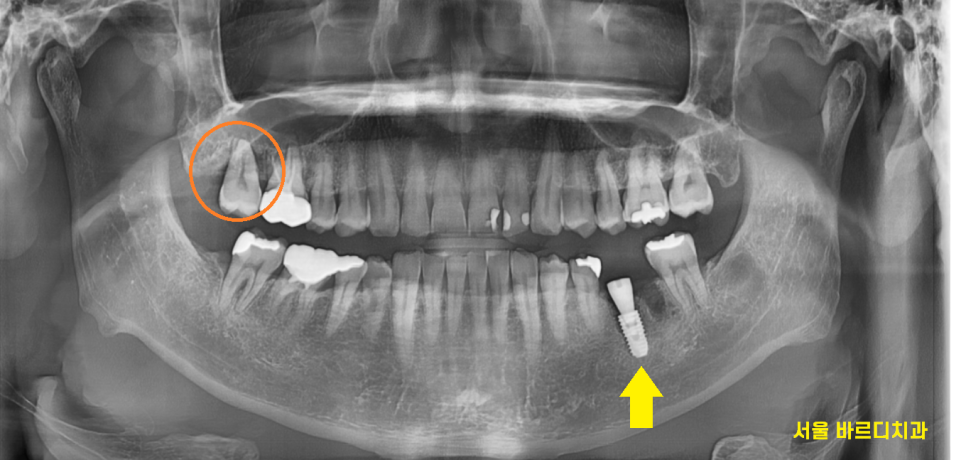

왼쪽 아래 임플란트를 치료중에

환자분께서 오른쪽 불편함을 호소하셨습니다.

강동구 임플란트 과정 중에

왼쪽이 치아 1개가 없어서

오른쪽 치아로 주로 씹다보니

왼쪽 아래 강동구 임플란트 치료중

계속하여 경과관찰을 하였는데요.

오른쪽 아래 임플란트 치료가 끝나자마자

왼쪽 강동구 임플란트 식립하였습니다.